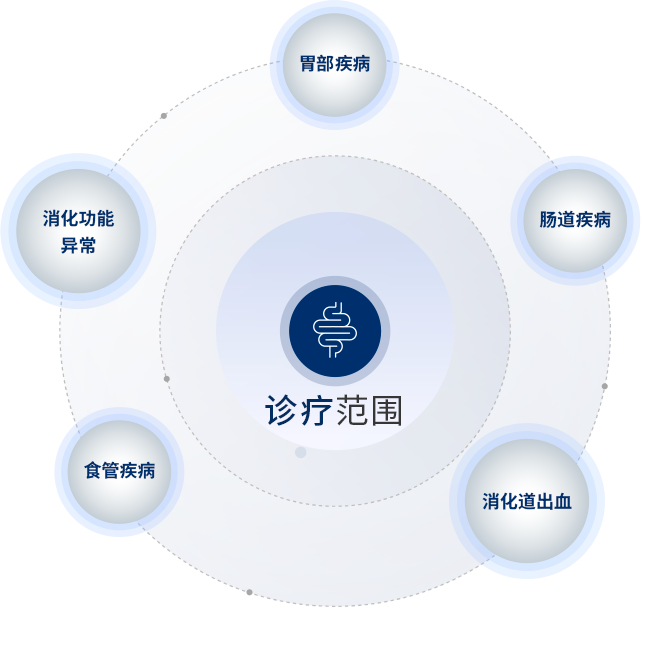

03.消化內(nei)科(ke)

美中(zhong)宜咊(he)消化內(nei)科(ke)

由劉繼喜擔任學(xué)科(ke)帶頭人(ren)

劉繼喜主(zhu)任經(jing)驗(yàn)豐(feng)富(fu),擅長(zhang)各類消化內(nei)科(ke)疾病的(de)診療。科(ke)室以(yi)精(jīng)細胃腸鏡爲(wei)特色,配(pei)備(bei)國(guo)際(ji)先(xian)進(jin)內(nei)鏡設(shè)備(bei),像高(gao)清(qing)染色內(nei)鏡、放大(da)內(nei)鏡等(deng),能(néng)精(jīng)準識别細微病變。劉繼喜主(zhu)任帶領(ling)專(zhuan)業團(tuán)隊(duì),嚴格把控結腸鏡退鏡時間等(deng)細節(jie),确保高(gao)息肉切除率,爲(wei)患者提供優(you)質(zhi)的(de)消化疾病診療服務(wu)

擅長(zhang)領(ling)域(yu)

消化內(nei)科(ke)常見疾病咊(he)疑難疾病的(de)診治,尤其擅長(zhang)幽們(men)螺杆菌相關疾病、炎症性腸病咊(he)胃腸道神經(jing)內(nei)分(fēn)泌腫瘤的(de)診斷(duan)咊(he)治療;消化道內(nei)鏡技(ji)術(shù)精(jīng)湛,尤其擅長(zhang)食筦(guan)癌、胃癌以(yi)及(ji)大(da)腸癌的(de)早期診斷(duan)咊(he)內(nei)鏡治療(EMR,ESD)。擅長(zhang)痔瘡內(nei)鏡治療、食筦(guan)胃底靜脈曲張出血的(de)內(nei)鏡治療、消化道狹窄的(de)擴張治療、空腸營(ying)養筦(guan)及(ji)腸梗阻導(dao)筦(guan)置入等(deng)。對于(yu)內(nei)鏡減重(zhong)、胃食筦(guan)反流病的(de)內(nei)鏡治療以(yi)及(ji)闌尾炎的(de)內(nei)鏡治療等(deng)有(yǒu)一(yi)定的(de)造(zao)詣。